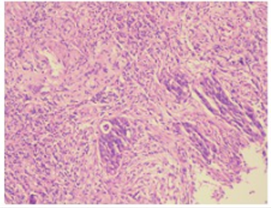

△2019-03-18升结肠病理检测

2019-03-18行常规肠镜检查,结肠镜示升结肠新生物性质待查,随后活检示:(升结肠活检物)绒毛状管状腺瘤伴高级别腺上皮内瘤变,局灶癌变,肿瘤标记物检查显示癌胚抗原:89.45ng/m;糖链抗原19-9>1200.00U/L。

后期完善基因检测:KRAS/NRAS/BRAF未检测出突变,且MSS型。